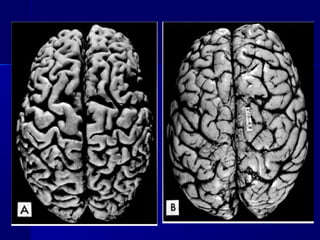

Atrophy of the brain

- Atrofia senil. Disminución del tamaño de los

órganos, envejecimiento “fisiológico”

MecanismosMecanismos

 Disminución de la síntesisDisminución de la síntesis

 Mecanismos endocíticos: vacuolas autofágicas.Mecanismos endocíticos: vacuolas autofágicas.

Gránulos de lipofuscina que cuando alcanzan unaGránulos de lipofuscina que cuando alcanzan una

cantidad suficiente hace que el órgano adquiera uncantidad suficiente hace que el órgano adquiera un

color marrón. (atrofia parda, corazón y cerebro)color marrón. (atrofia parda, corazón y cerebro)

 Vía proteasomas: proteólisis aceleradaVía proteasomas: proteólisis acelerada